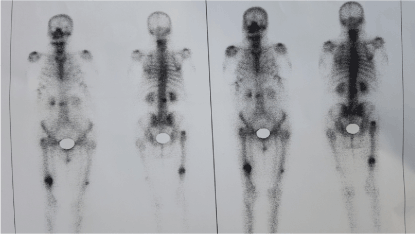

According to the newest guidelines of the ASBMR (American Society of Bone and Mineral Research), the patient underwent intramedullary nailing of the right femur and was instructed to discontinue bisphosphonate along with non-weight bearing of the left lower extremity [17-19]. Although a bone scan was conducted for further investigation of the incomplete fracture and the presence of other imperfect fracture sites, no new lesions were found (Figures 2&3). After 6 weeks, there was a clinical improvement in the left femur and radiographic appearance of callus, thus excluding the prophylactic intramedullary nailing of the left femur. The union of both fractures developed normally both for the right femur which was treated with intramedullary nailing and the left femur where conservative treatment was selected. The union of the right femur was not affected by the fact that the distal locking screw was not centered in the nail hole. The radiographic monitoring of the bone healing was conducted at 3, 6 and 12 months after the first treatment took place (Figures 4&5).

Figure 2. Bone scan

Figure 3. Bone scan